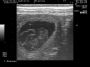

חדשות מרגשות יש הערב. לפני מספר דקות בלבד סיימנו את סריקת האולטרא סאונד של מארם,שהיום עומדת על יום 30 להריון מההרבעה הראשונה. מארם שכבר מראה סימנים חיצוניים היתה ברורה שבעלת שגר גדול, על אף שבסריקה הקודמת ניתן היה לאתר רק 6 עוברים בתוך קפלי המעי, היום ניתן היה לראות בבירור מושלם 9 גורים בריאים, שלמים ובעלי דופק מרגש של 345 פעימות לדקה בממוצע.